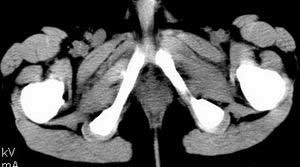

| 患者,男,9岁,因右下腹包块入院,血象不高,不规则发热,常超40度。 平扫: ![]() ![]() ![]() ![]() ![]() ![]() ![]() ![]() ![]() ![]() ![]() ![]() ![]() ![]() ![]() ![]() ![]() ![]() 增强: ![]() ![]() ![]() ![]() ![]() ![]() ![]() ![]() ![]() ![]() ![]() ![]() ![]() ![]() jiajie发言:骶椎右前区不规则软组织肿块,边缘光整,密度均匀,增强后均匀强化,右腹股沟区可见肿大淋巴结,临床有时发热,考虑淋巴瘤,儿童盆腔肿瘤应与神经母细胞瘤和横纹肌肉瘤鉴别。 longzhanghui发言:印象:盆腔右后壁不规则软组织肿块,并向前延伸.似为多个肿块融合,呈中等强化.初步考虑淋巴瘤. 听蝉观竹发言:右侧髂内、外组淋巴结肿大,从其形态和融合的情况看,同意大家意见-----考虑恶性病变,但是9岁男孩还要注意检查睾丸情况,有无隐睾? 常常类似情况是隐睾发生精原细胞瘤淋巴结转移,这个病例也要注意这一点!!! 广东凌发言:大家好,在这里我想说一下个人观点,我建议上传图片的同志能否辛苦一点就是把病史和图片都上传完整一点,比如这个病人的腹膜窗,并且这个病人的肠道的准备也是不怎么好,就从现有的质料看:病灶属于淋巴结肿大当无大的争议,有融合趋势,其内无坏死,边缘强化为主,故考虑:淋巴瘤!建议用腹膜窗看一下和肠道的关系! 阿圣发言:病灶属于淋巴结肿大当无大的争议,有融合趋势,其内无坏死,边缘强化为主,故考虑:淋巴瘤 结果是:淋巴瘤 病例来源:ct762。由宁静致远发布: http://www.radinet.com.cn/forum_view.asp?forum_id=4&view_id=2182 |